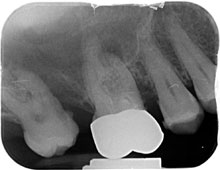

• Das Pulpenkavum wird eröffnet und die Kanaleingänge dargestellt. Je nach Zahn können mehrere Wurzelkanäle vorhanden sein. Eine grobe Faustregel ist pro Wurzel ein Kanal, in der Praxis zeigt sich aber oft, daß eine Wurzel auch mehrere Kanäle haben kann. Siehe Röntgenbild: